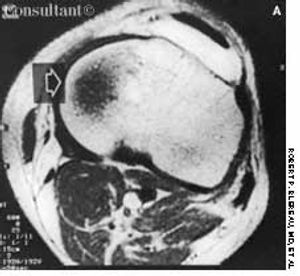

A 41-year-old man fell 3 ft into a bilge; he landed on his left leg and experienced immediate generalized pain in that knee. Three days later, he consulted his physician, who found minimal effusion in the knee and tenderness of the medial collateral ligament (MCL). No abnormalities were seen on plain x-ray films.

A 91-cm (3-ft) fall into a bilge sparked significant pain in the left knee of a 41-year-old man who landed on his left leg. Three days later, physicians found minimal effusion in the knee and medial collateral ligament tenderness.